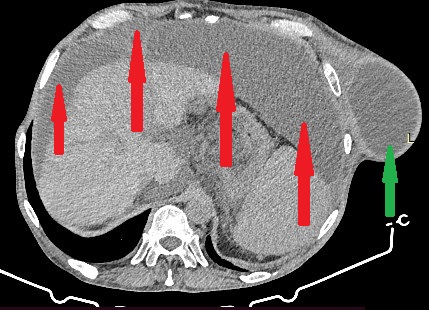

CT άνω κοιλίας με σκιαγραφικό που αναδεικνύει συστάδα διατεταμένων ελίκων λεπτού εντέρου στο κέντρο δίνοντας εικόνα κουνουπιδιού (βέλη) (Ευγενική παραχώρηση Dr. V. Penopoulos)